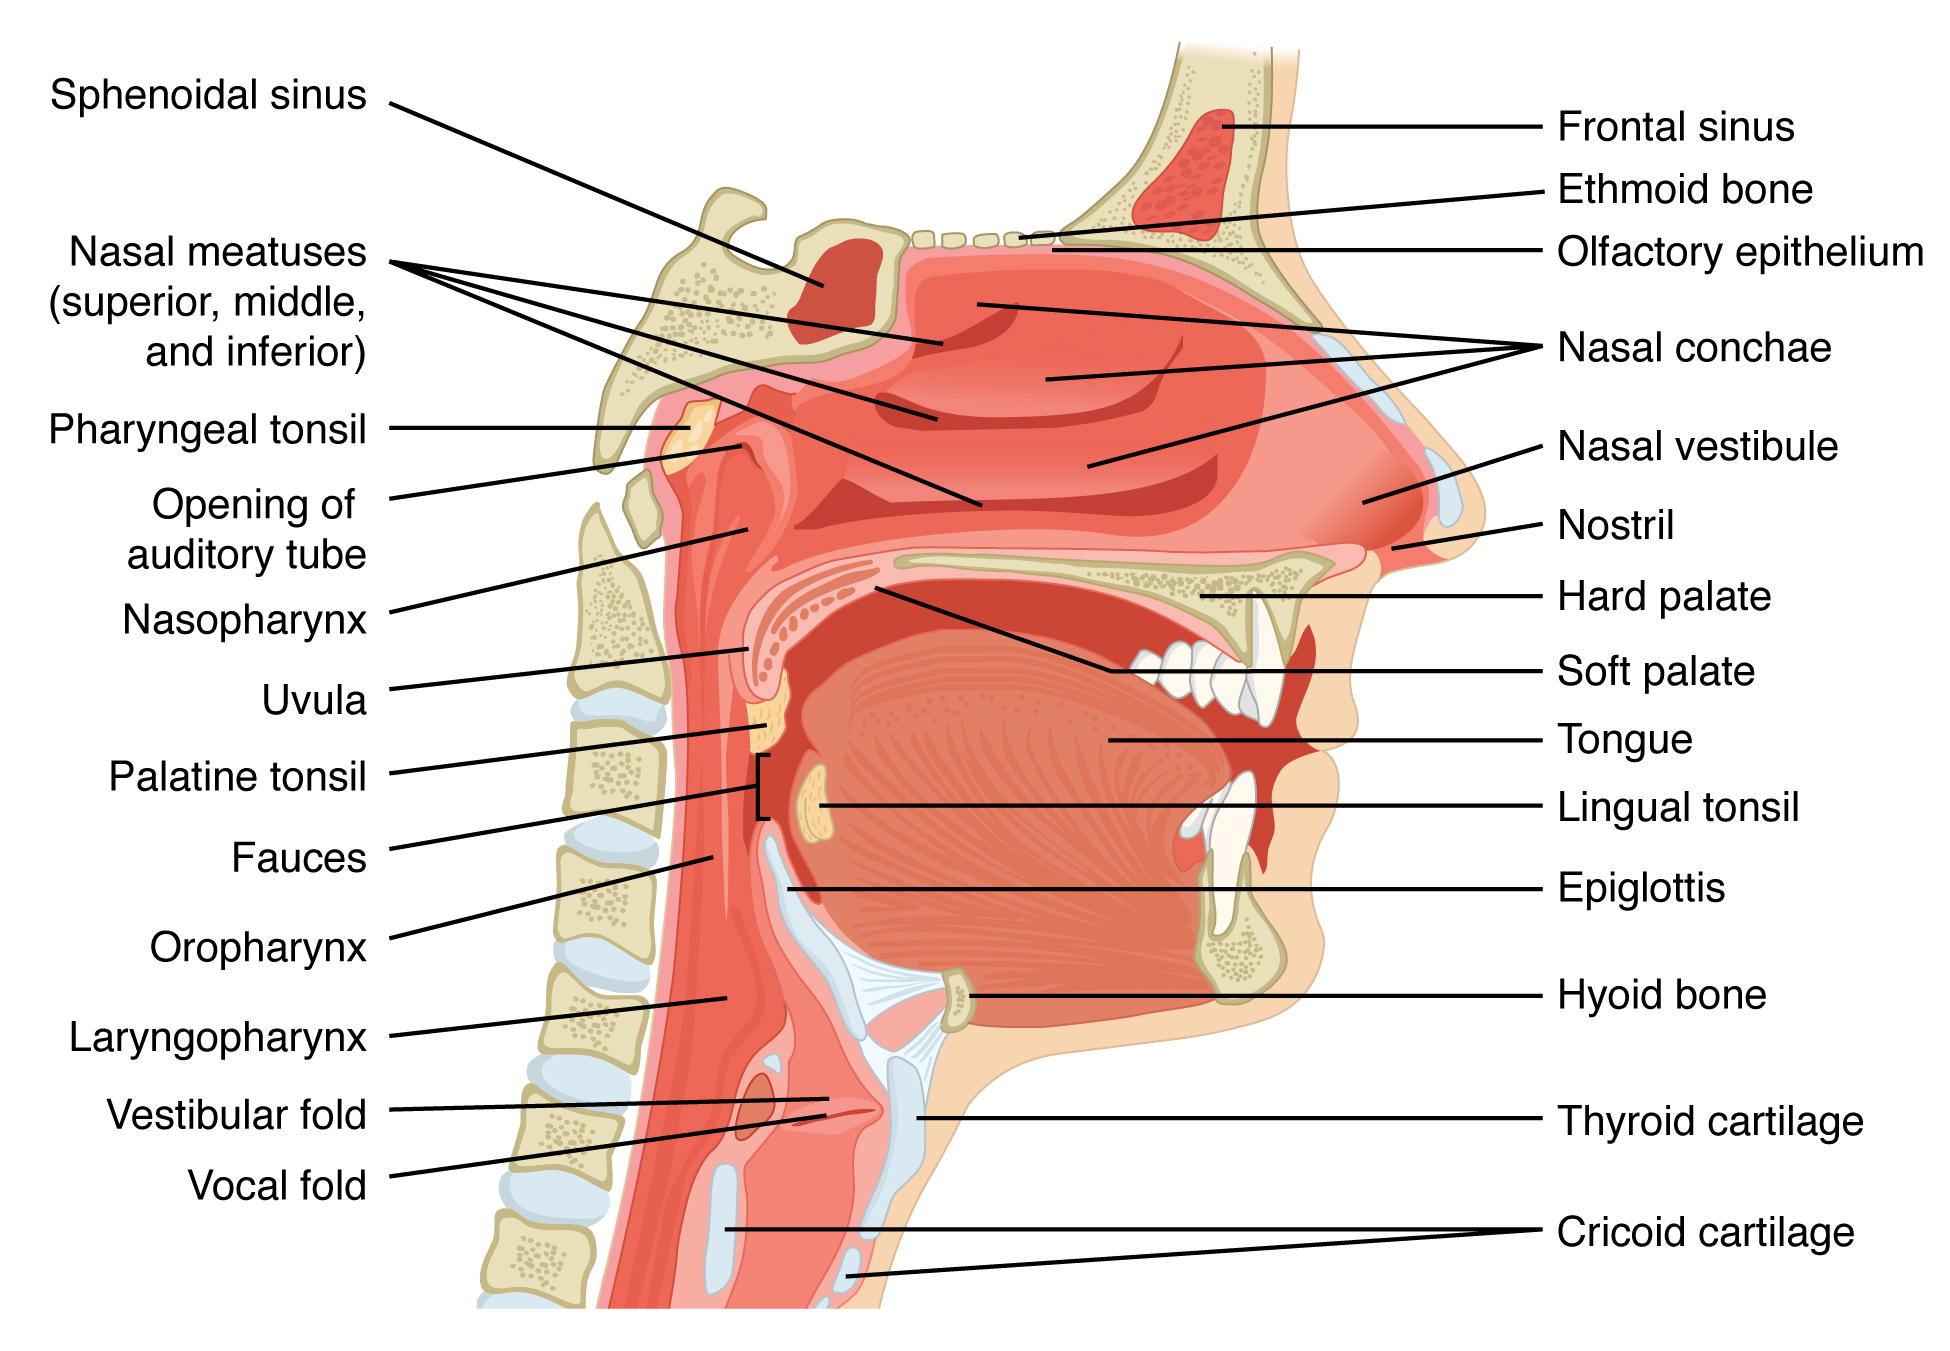

1 – Review of Respiratory System Anatomy